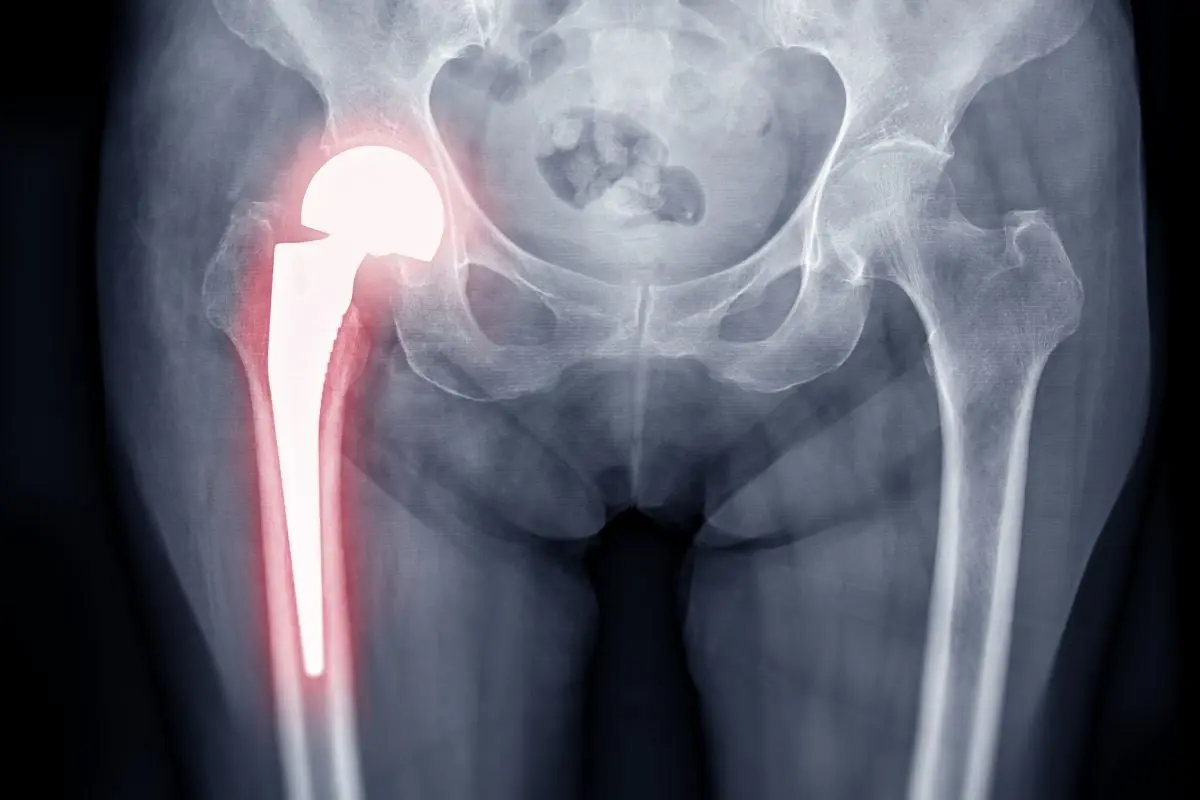

Hip replacement surgery, also known as total hip arthroplasty, involves replacing a damaged hip joint with an artificial implant designed to restore normal movement and reduce pain caused by conditions such as osteoarthritis, hip fractures, or joint degeneration. Modern surgical techniques, including minimally invasive approaches and high-quality prosthetic materials like titanium and ceramic implants, allow patients to recover faster and return to their normal routines with significantly improved quality of life.

During the surgery, the orthopedic surgeon removes the damaged parts of the hip joint and replaces them with a hip prosthesis made of durable materials such as titanium, ceramic, or medical-grade plastic. These artificial components are designed to replicate the natural movement of the hip, helping patients move more comfortably and with less pain.

The prosthetic hip usually consists of three main components:

- A metal stem placed inside the thigh bone (femur)

- A ball component that replaces the damaged femoral head

- A socket component that replaces the damaged hip socket

These components are made from durable materials such as titanium, ceramic, or medical-grade plastic, allowing the artificial joint to move smoothly and withstand years of use.